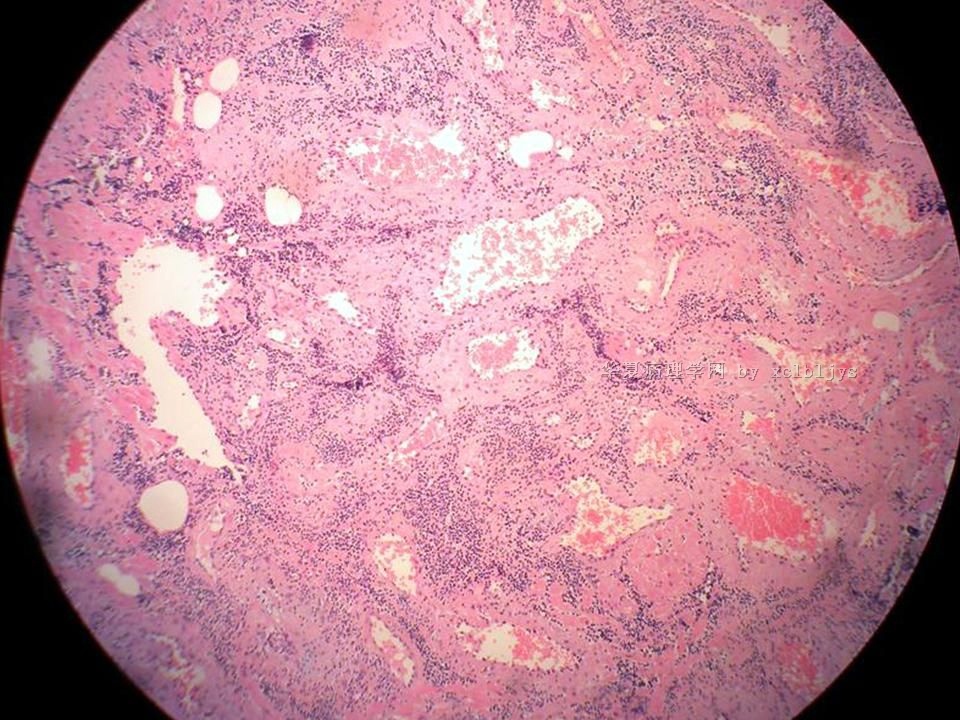

| 以下是引用xclbljys在2010-12-22 17:20:00的发言: 本例我们科室医生有两种意见:一种是炎性假瘤;第二种意见是炎性假瘤伴局限性Wegener肉芽肿。 依据是眼眶内肿块含有大量的动脉内膜炎改变,浸润的炎细胞有淋巴细胞、浆细胞、嗜中性粒细胞和嗜酸细胞等,如图16所示,炎细胞已经浸润动脉壁全层,应符合坏死性小动脉炎,但尚不能确定动脉壁弹力纤维层的破坏。 请各位老师点评! Wegener肉芽肿多发生在上呼吸道、肺、肾脏和皮肤等器官与组织。坏死性血管炎需证实有纤维素样坏死。小动脉炎多在皮肤病变比较明显。本例的小动脉炎或许是炎症引起的继发性改变。需要完善病史,查血免疫指标,看有没有系统性疾病。如果没有系统性疾病,还是考虑慢性炎症继发小血管炎。

血管炎是正常营养/供给血管的炎症性病变,而不是增生血管的炎症。血管炎往往有明显的临床相应症状,如皮疹。典型的Wegerner肉芽肿病有三联症(上呼吸道、肺、肾脏病变)。血管炎不仅是有炎症细胞,同时有血管壁的变性、坏死(纤维素样), 内皮细胞的变质和增生,炎症细胞浸润(包括中性粒细胞、淋巴细胞、组织细胞、嗜酸性细胞、巨细胞等)。不同类型的血管炎累及的血管大小、炎症细胞的类型、有无肉芽肿改变都不相同。血管炎的病因可以是过敏、自身免疫、胶原性疾病、感染等多种因素。